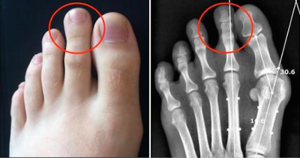

Aceste probleme vă dau bătăi de cap? Nu știți cum să faceți față zilnic acestei suferințe cu care vă confruntați? Am găsit remediile pentru a trata monturile

Din învăţămintele populare am învăţat ca remediile din natură fac bine în cazul multor probleme[...]